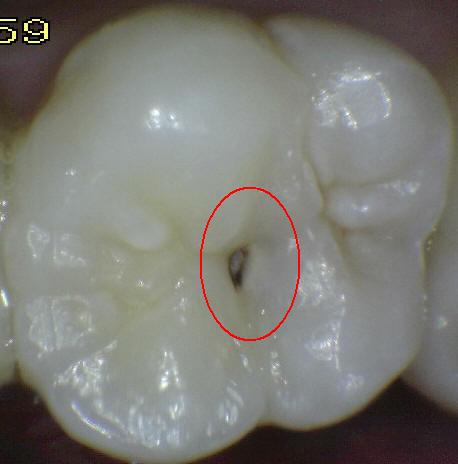

Código 1: Primer cambio

visible en el esmalte seco

- Cuando se ve húmeda no hay evidencia de

cambio en el color atribuibles a la actividad de caries, pero después

del secado con aire por 5 segundos, una opacidad de caries o cambio de

color (mancha blanca o lesión marrón) es visible, lo cual no es consistente con

la apariencia clínica del esmalte sano, el cambio de color se

limita al fondo de la fosa o fisura. La aparición de estas áreas

de caries no es consistente con la de las fosas y fisuras teñidas como

se define en el código 0.